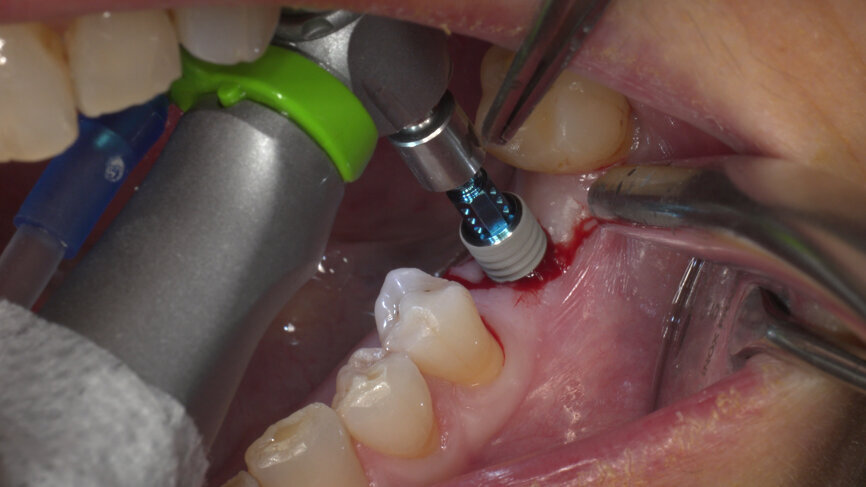

Under local anaesthesia, a flapless implant surgery technique was performed in position #36. Owing to the quality of the bone, staged drilling with continuous saline irrigation was performed in order to obtain a proper, safe insertion torque (Figs. 2–7). One implant (BLT, Regular Neck, Roxolid, ⌀ 4.8 × 10.0 mm) was placed, and a torque of 42 N cm was applied (Figs. 8–11).